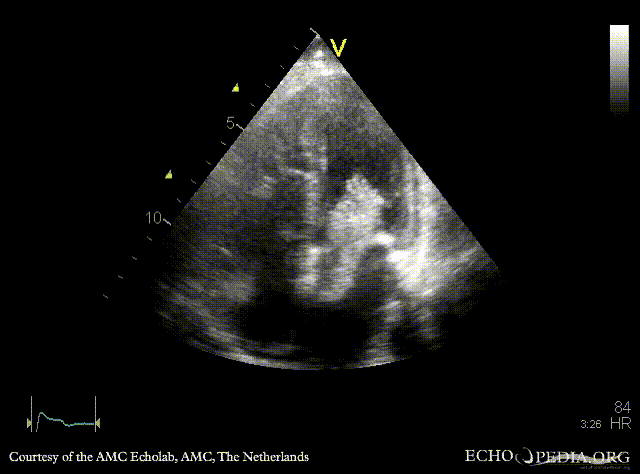

Giant myxoma in left atrium

A4CH